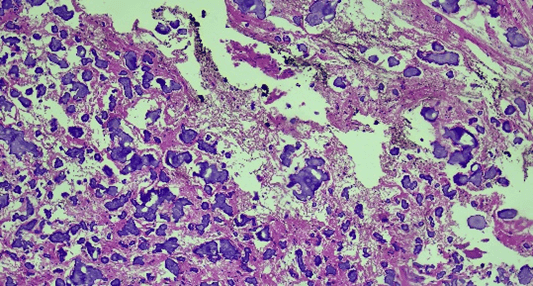

In the anatomopathological study, the lesion was well circumscribed, not encapsulated, and composed predominantly of spindle cells, with indistinct cytoplasm. In addition, it presented a delicate and fibrillar stroma with a prominent presence of calcified bodies, similar to psammomas, uniformly arranged (Figure 3). Immunohistochemical evaluation revealed cells diffusely positive for glial fibrillary acidic protein (GFAP), S-100, epithelial membrane antigen (EMA), and vimentin (Figure 4), and negative for progesterone receptor, pan-cytokeratins (AE1/AE3), Ki-67 (MIB-1), synaptophysin, and IDH-1. On CD34, no vascular anomalies were observed, and the reticulin stain revealed intact and parallel fibers. Based on these findings and on those from the imaging studies, the diagnosis of CAPNON was established. This diagnosis was confirmed by three other board certified pathologists, including a colleague from the University of Toronto.

Figure 3: Photomicrograph (hematoxylin and eosin staining) showing spindle cells interspersed with several calcified bodies similar to psammomas (10x magnification).

According with the review of the literature, the histopathological findings of the CAPNON include the pattern observed in our patient, which was described in several other cases, especially the scattered calcified basophilic bodies within spindle cells in a delicate and fibrillar stroma without mitoses. Other patterns that can be found are the chondromyxoid matrix in a nodular pattern, the osseous metaplasia, the foreign-body reaction with giant cells, and the psammoma-like bodies, of which only the latter was observed in our patient [4, 19, 27-31]. It is important to note that these characteristics may also be seen in entities such as chordomas, chondrosarcomas, osteosarcomas, meningiomas or schwannomas, which should be considered among the differential diagnoses.